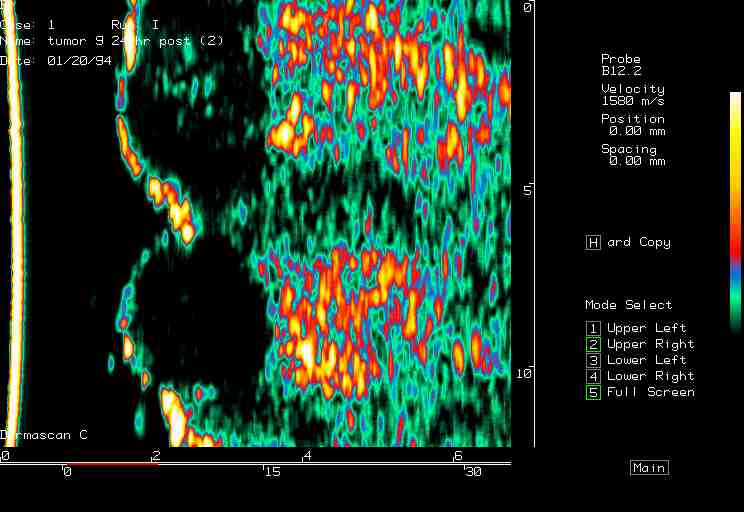

| Tumors |  BCC on the ear |

BCC, various sites |

BCC pre PDT |

BCC post PDT |